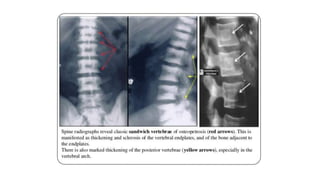

Osteopetrosis. Radiograph of skull shows diffusely increased density (A). Radiograph of bilateral femurs show

obliteration of medullary cavity and Erlenmeyer flask deformity (arrow, B). Also note sandwich vertebrae

(arrow, C) bone-within-bone appearance in pelvis (arrow, D) and increased density in hand bones (E).